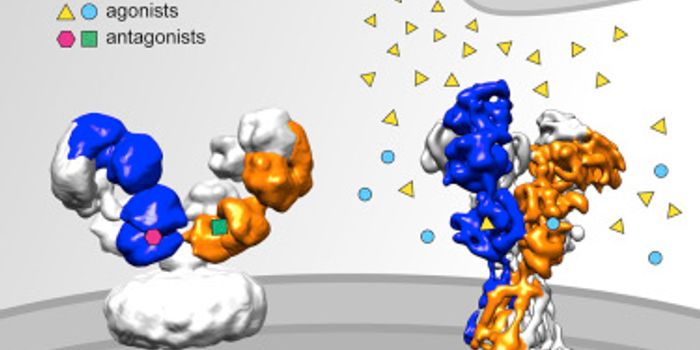

APR 14, 2016NeuroscienceGlutamate is the main excitatory neurotransmitter and is essential for many important processes in the brain. In accorda ...